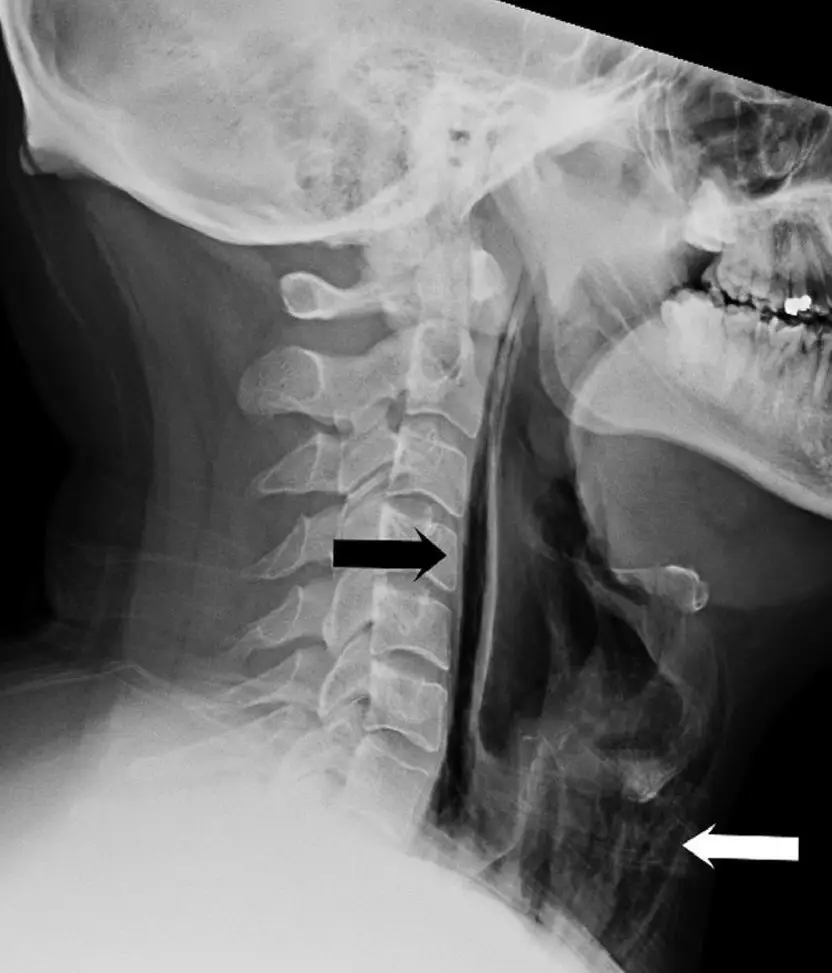

Upon a physical examination, health professionals found 'swelling and tenderness' in his neck with an X-ray later revealing that 'streaks of air' had become trapped in parts of the man's throat tissue.

These pockets of trapped air effectively meant the man had ruptured his own throat.